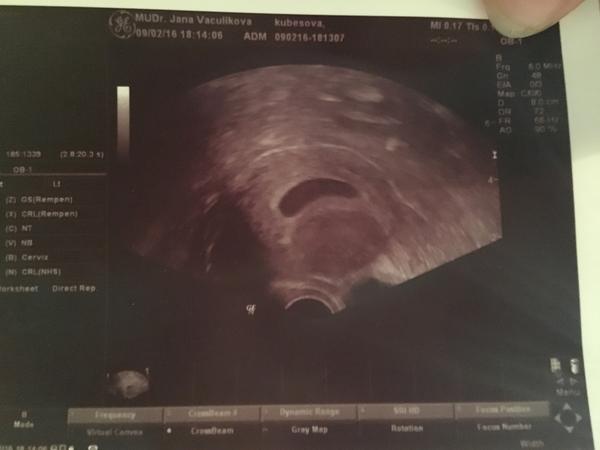

@slunicko156 tak tohle je krásný gestační váček - uložený v děloze - paráááda - tak mimoděložní těhotenství to není.který DC jsi na tom UZ? Ono totiž je to i tom, jak se natočí sonda atd. 🙂 jinak první je gestační váček, pár dní na to žloutkový s malou čočkou, kde se ukazuje srdeční akce. tzn., že pokud jsi cca 5 týden, tak na srdíčko tě pozvala správně 🙂 pokud se bojíš, zda je to normální nález - tak je to normální - gestační váček je pravidelný

@slunicko156 jinak pro vysvětlení - ten takový tvar rohlíčku, to je gestační váček🙂 a je uložený v děloze - to je kolem toho váčku ohraničené bíle nahoře

@megy no podle výpočtu mého jsem byla na ultrazvuku 6+2tt ale těžko říct, poslední MS byla 24.12. 🙂, jo tak uz je mi to jasné uf 🙂

@slunicko156 věz, že spermie jsou dost životaschopné - já podle všeho otěhotněla tenkrát úplně jinak než jsem si myslela 😀 u tebe to sedí úplně - jestli 10.1. byl PS, pak cca i podle životnosti spermií jsi mohla otěhotnět cca až 13.1 a to bez problémů 😀 - než se to dostane do dělohy a uhnízdí, tak to bývá tak 5-7den, tudíž tak 20.1. než se začne tvořit hcg, tak to odpovídá tomu testu, co máš a to 22.1.což je cca 27DC. 8.2 jsi byla 44DC - podle toho to odpovídá cca 6+2 - tak jak píšeš, ale mimčo bude asi kvůli té posunuté ovu o cca 3 dny mladší tipuju, takže UZ by odpovídalo přesně stáří 5+6 - což je absolutně normální nález. Já vím, že jsem byla tenkrát na UZ měla jsem taky spočítáno, že bych měla být víc a to mě dr. dost překvapil, že to bylo mladší 🙂

@slunicko156 jo jinak jsi mě donutila ti podat důkaz - přidávám ti fotku z druhého těhotenství, kdy jsem si ji dokonce popsala, že jsem podle MS měla být 6+2 a podle uz jsem byla 6+0 😀